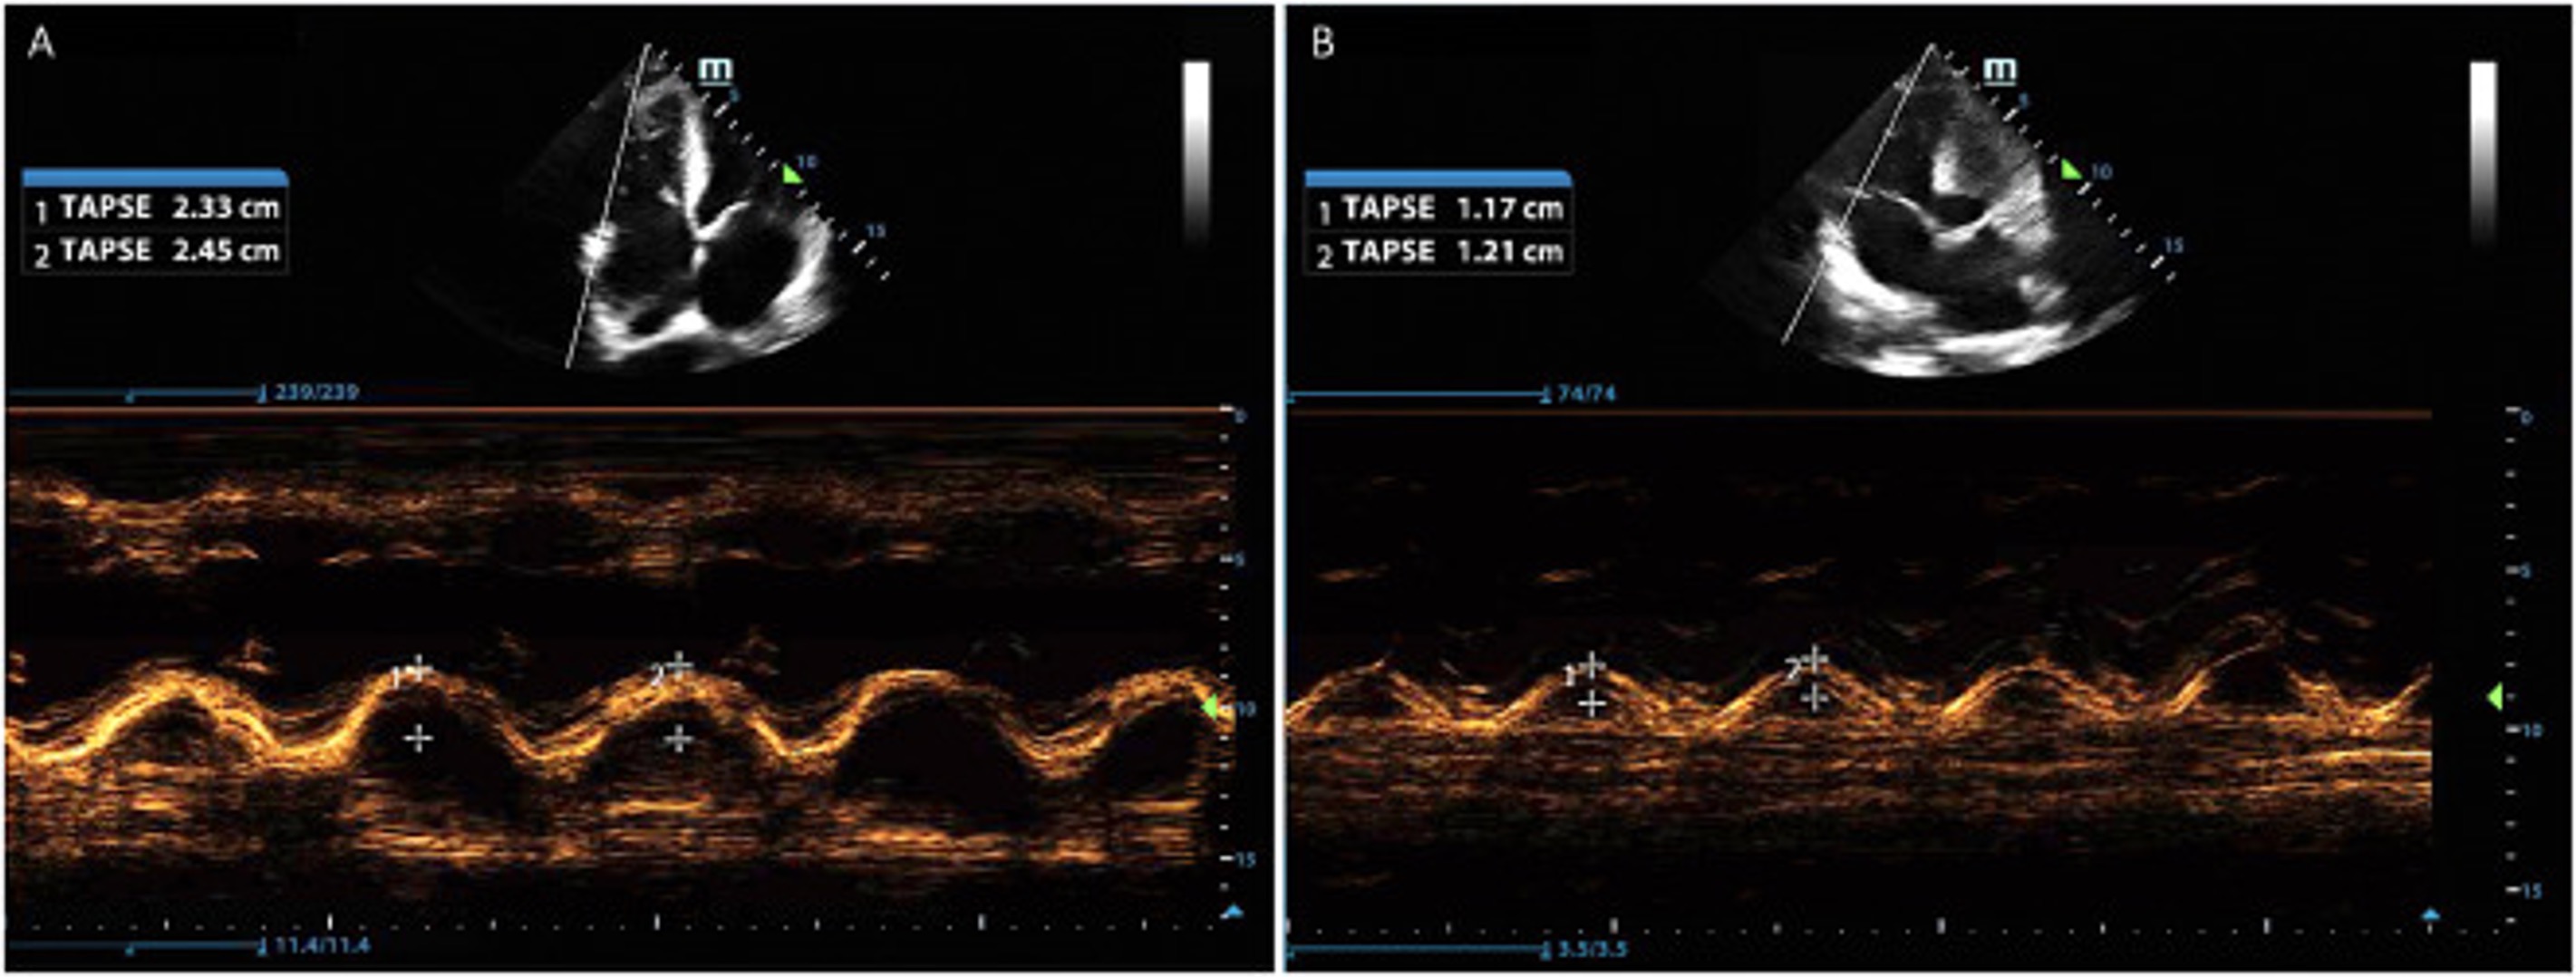

Tricuspid Annular Plane Systolic Excursion (TAPSE) < 17mm / 1.6cm => RV systolic dysfunction. Normal mean is 24mm +/- 3mm.